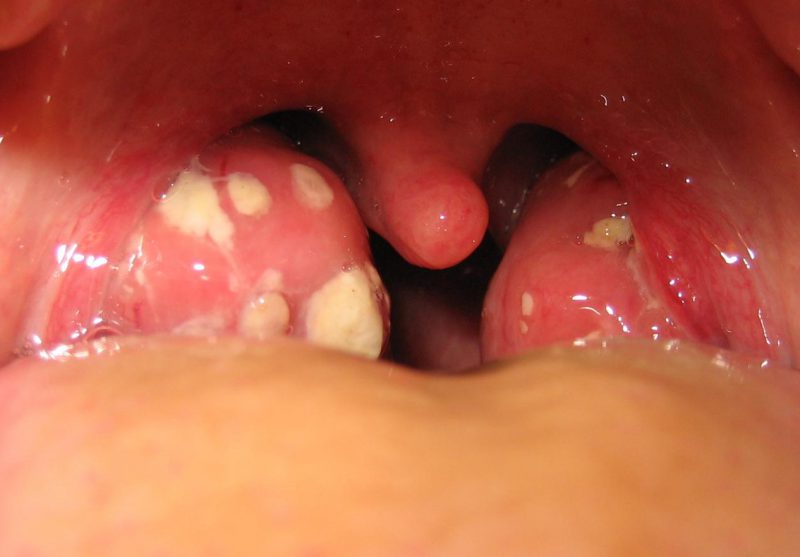

воспаление ЛОР-органов |

стафилококковая ангина |